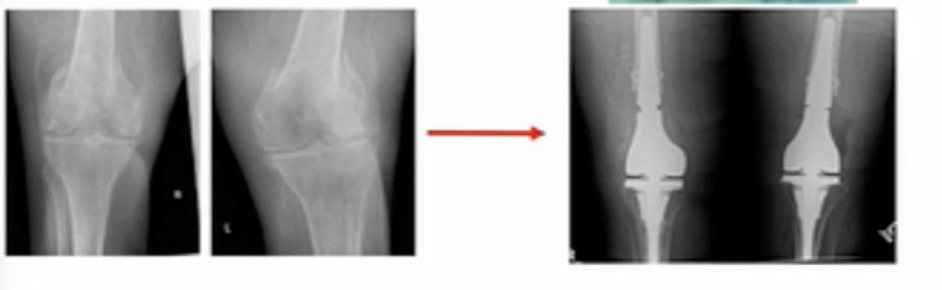

Lastly, this is a unique case that we took care of at our institution. (Figure 3) This may have been on the aggressive side, but she had bilateral distal femur fractures and multiple medical comorbidities including severe heart disease and lung disease, which triggered a multidisciplinary team discussion and patient consultation. We had our trauma, joint replacement (me), physical therapy, and medical doctor as a team to advise the patient of all options and outcomes. We presented options for fixing versus replacing and ultimately the patient’s preference was to go for arthroplasty. We performed bilateral reconstructions using the OptiStem in this patient. She’s about six months out and doing well so far.